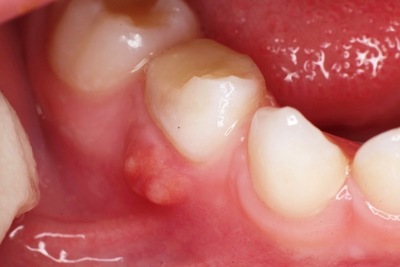

Фото 4. Гранулёма, возникшая из-за периодонтита. Представляет из себя припухлость на десне.